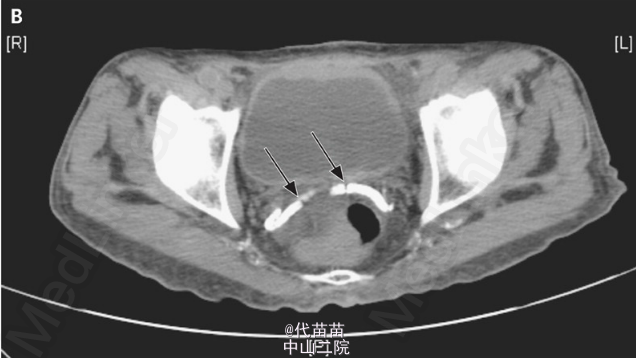

NEJM临床图片:输精管钙化

60岁男性患有晚期糖尿病肾病与甲状旁腺机能亢进,为对其肾结石情况作评估进行放射线检查。结果没发现肾积水或肾结石,但双侧输精管都出现钙化。糖尿病人出现输精管钙化是常见的,可导致不育。此病例并无针对钙化的治疗,只需做好糖尿病和肾病的治疗。